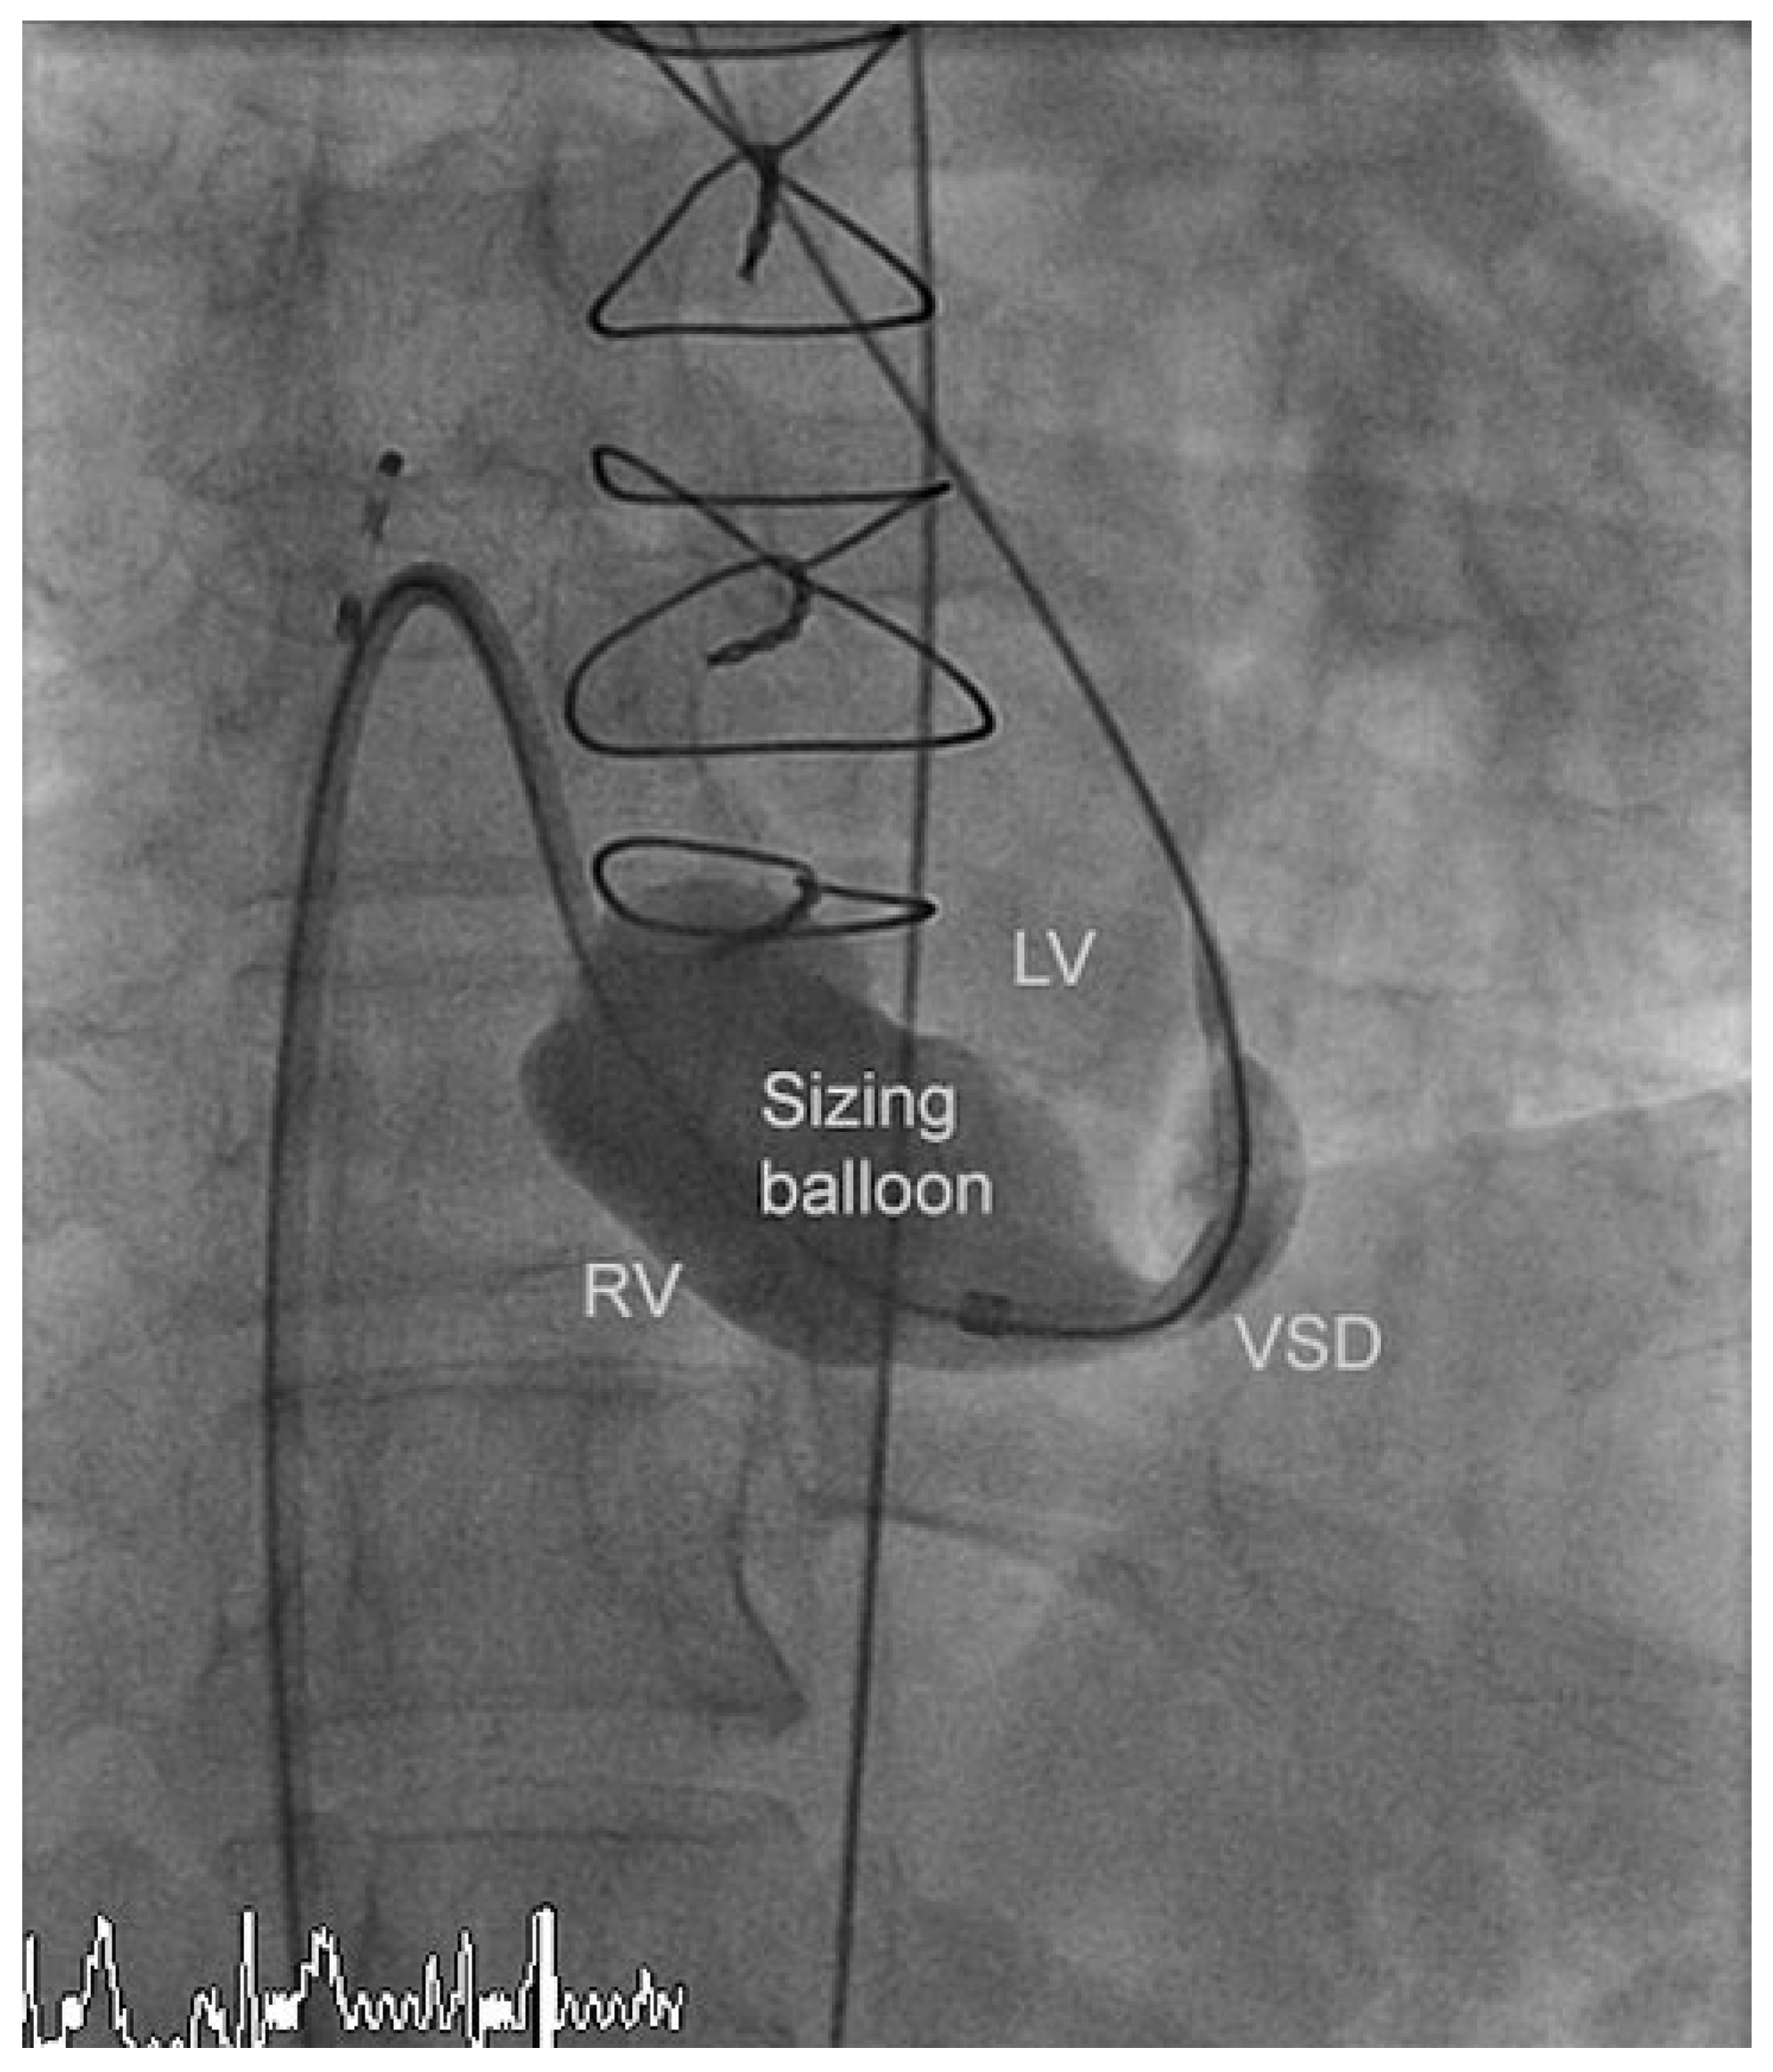

The residual VSD was identified with left ventricular contrast injection and the defect was crossed from the left ventricular side using a guide wire which was snared in the pulmonary artery and exteriorized thus creating an arteriovenous loop. The VSD was measured using a 34 mm sizing balloon (St. Jude-AGA) (Figure 1). A 14 mm Amplatzer muscular VSD occluder (St. Jude-AGA) was implanted through an 8 F TorqVue sheath (St. Jude-AGA) inserted through the right femoral vein (Figure 2). Adequate position was confirmed under fluoroscopy with contrast injection into the left ventricle (Figure 3). The procedure was performed without TEE and under local anaesthesia.

Figure 1. Measurement of the apical VSD by means of a sizing balloon (34 mm). LV (left ventricle), RV (right ventricle), VSD (ventricular septal defect).